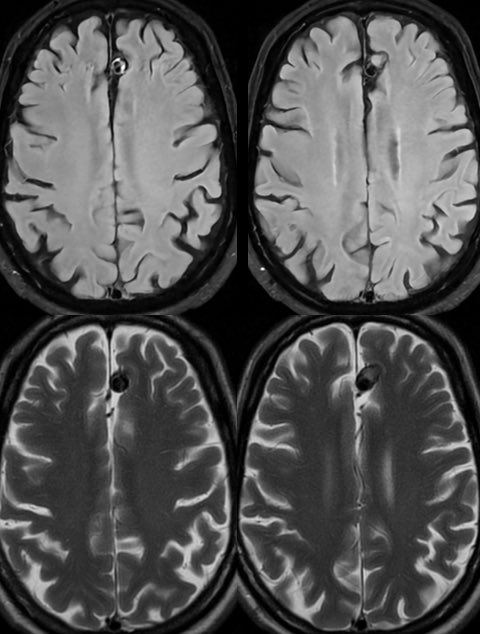

📢 Following the publication of the #BraTSAfrica dataset & with the upcoming #BraTS2025 Challenge, we’re taking the next step: 🧠 Help shape the Brain Tumor Imaging Protocol Africa Project (BTIP-Africa) 🎯 Goal: Co-create standard glioma imaging guidelines for African settings 📋 Take our 10-min survey ➡️ docs.google.com/forms/d/e/1FAI… 📄 BraTS-Africa paper: doi.org/10.1148/ryai.2… #GlobalHealth #Neuroimaging #Radiology #AIforGood @SARIMRadiologie @EEsrnm @GRadiologists @RadKenya @Radiology_SA @rigsudan @NigerianSIR @taraso_tz @RwandaMedicalAs